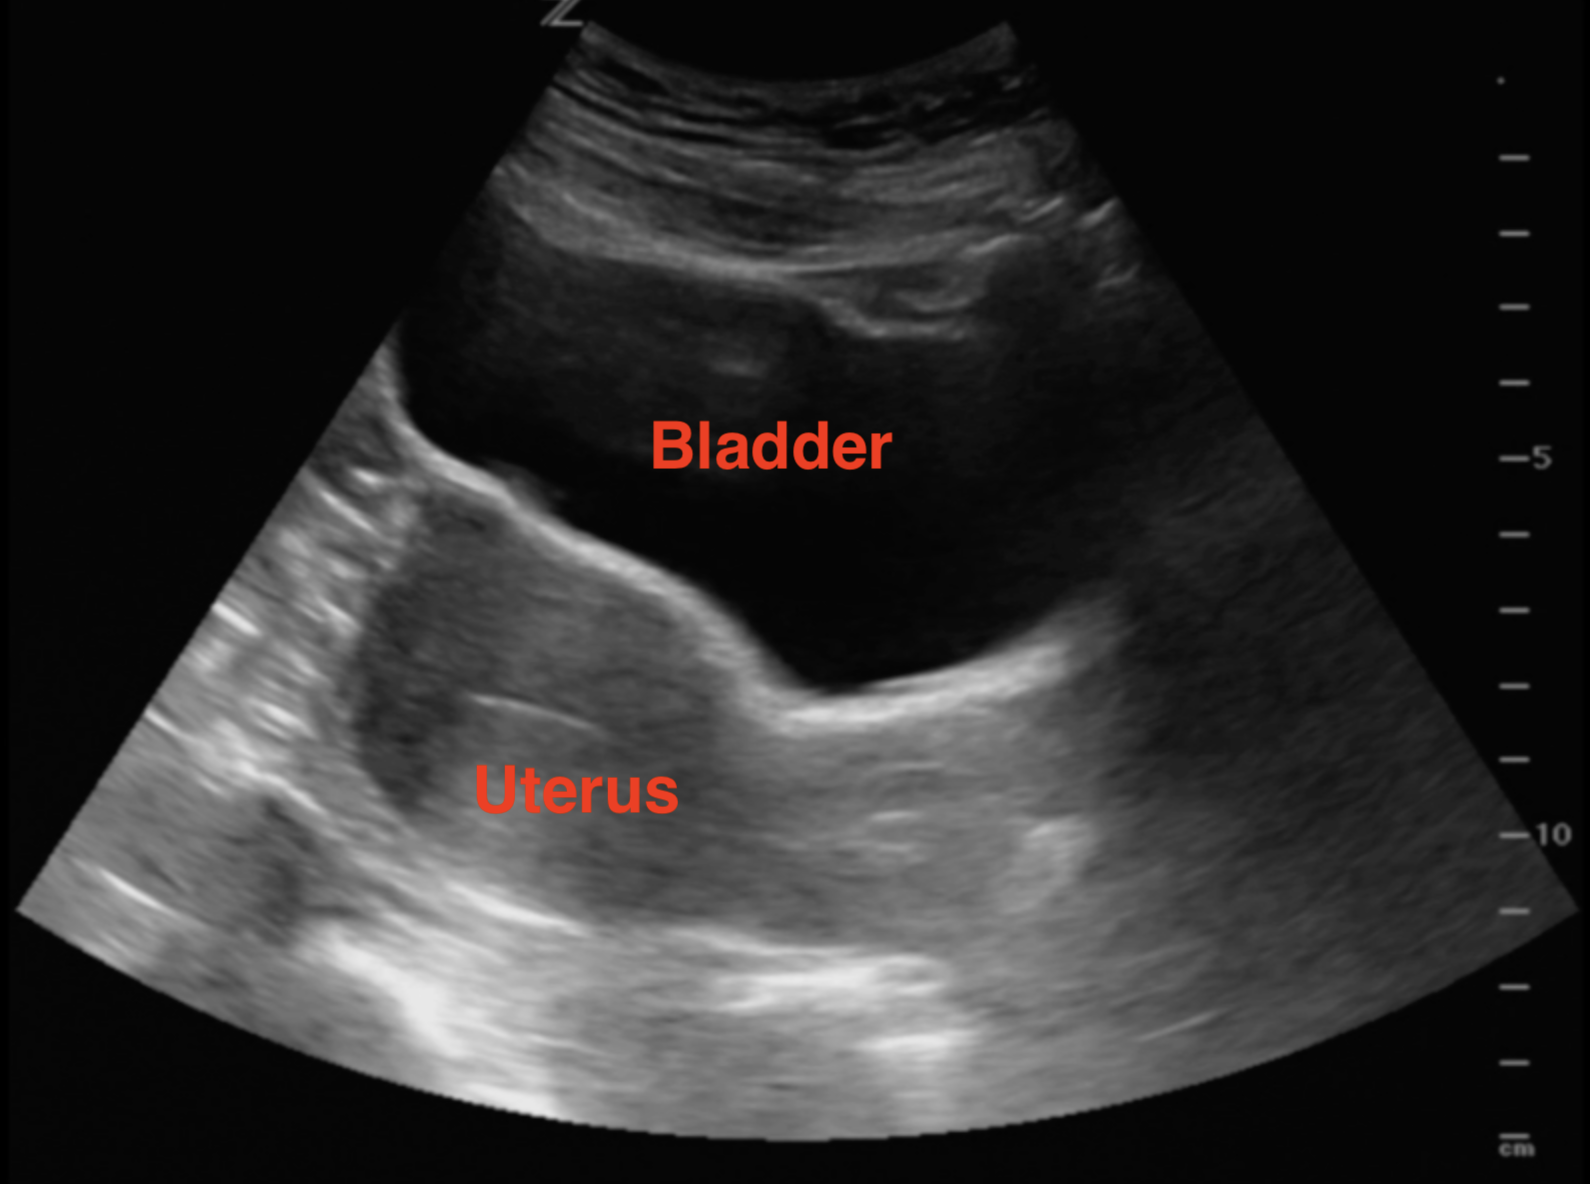

- In the transverse plane use the bladder as an acoustic window to identify the uterus. Fan all the way through by angling the beam towards then head and fan towards the feet. The endometrial stripe should be a hyperechoic line in the middle of the uterus.

- Illustration 3. Illustration of transverse approach and relevant anatomy. Probe indicator toward patient’s right (star)

- Illustration 4. Transverse view of pelvis

- Video 1. Transverse view with bladder anteriorly (on top) and uterus posteriorly